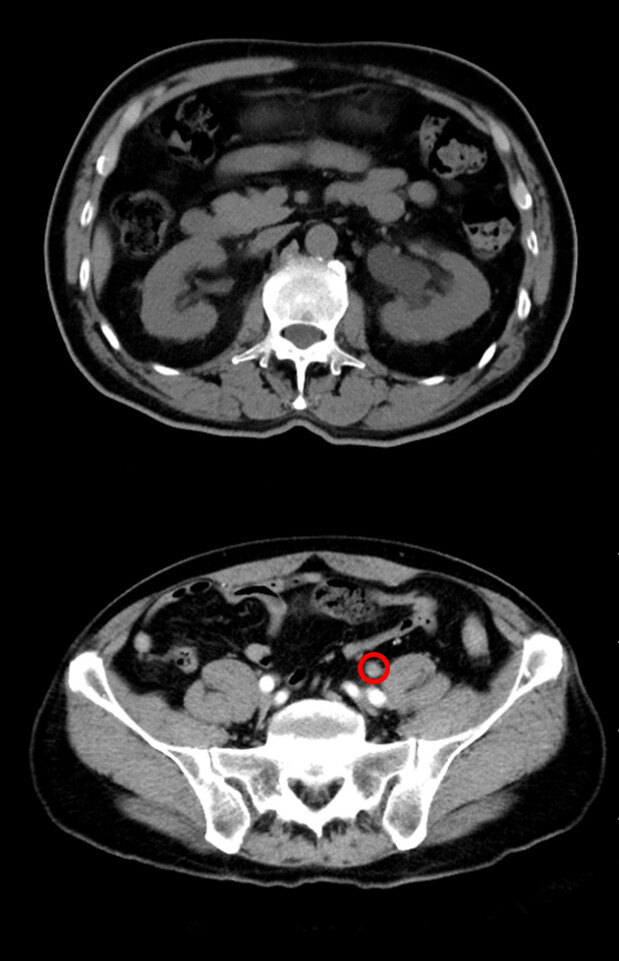

既往结石病史,当地医院ct提示左侧输尿管下段肿物,考虑肿瘤可能,左肾

图片尺寸1600x1200